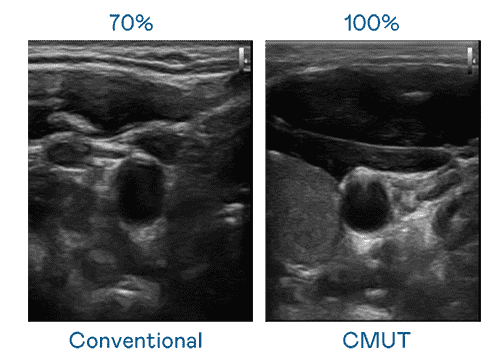

CMUT 技术是一种用电容式微机电元件来产生超音波讯号的技术。。。与传统 PZT 压电式技术相比,,,CMUT 频宽增加 30%,,,更宽频的超音波讯号让影像解析度大幅提升,,,,是实现高影像品质医疗超音波扫描、、促进精准医疗发展的关键技术。。。。

大频宽带来超清晰影像

超音波影像的解析度高低,,,首先取决于探头能发出的讯号频宽。。www.z6.com CMUT 可提供高清晰的超音波讯号,,,提供高频宽、、、高灵敏度、、、影像纹理细节更高的超音波影像,,,,协助医护人员缩短影像判读时间及利用精准的医疗影像进行诊断。。。